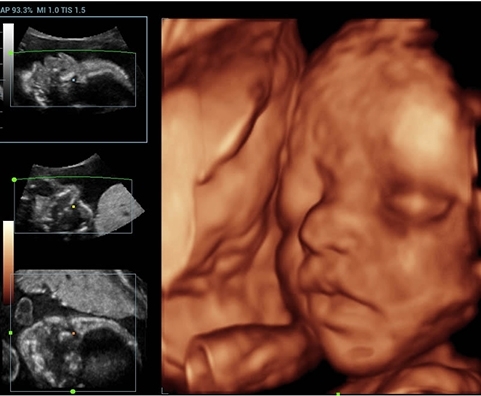

• Smart OB — программное обеспечение для автоматического измерения биометрии плода в акушерстве;

• Smart NT — программное обеспечение для автоматического измерения толщины воротникового пространства у плода;

• Smart Face — программное обеспечение для удаления артефактов и улучшения визуализации лица плода;

Изображения